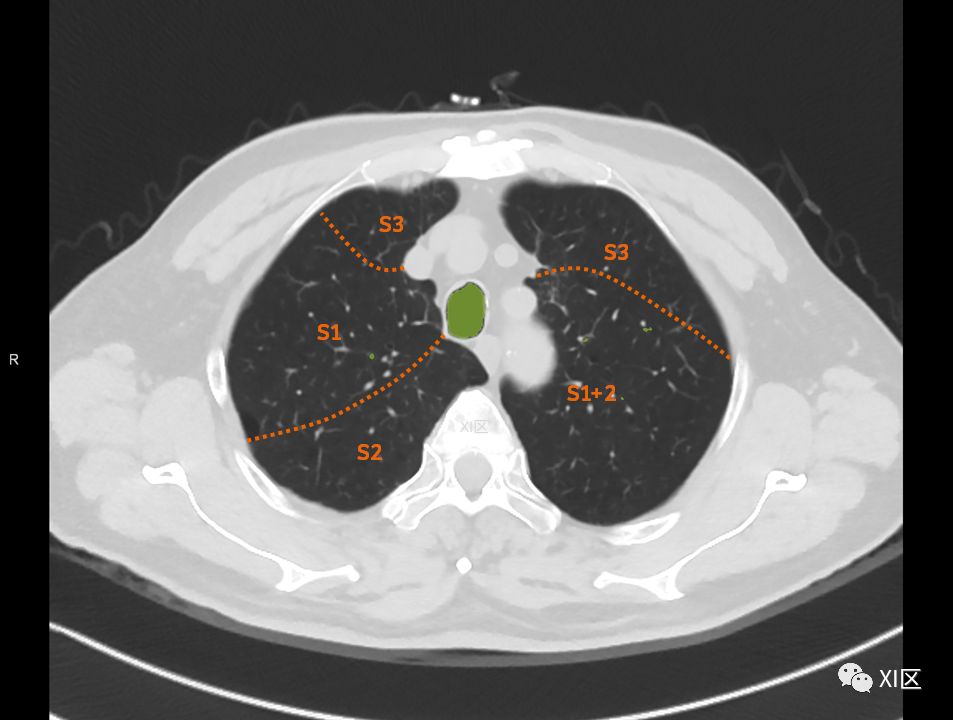

肺的断层分段示意图

在进行肺的分段时,可以上下观察浏览,沿着相应气管的走形可以更容易准确地进行分段。